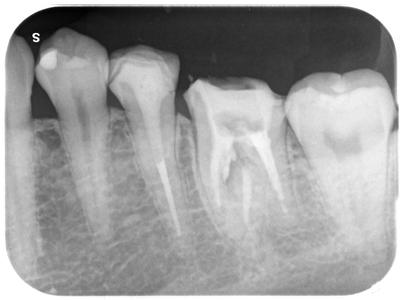

マイクロスコープ下、MTAによりリペアした。

2回の通院で痛みも全くとれた。

あと、補綴治療を予定している。

なお、マイクロスコープ下MTAパーフォレーションリペアは保険外診療となります。